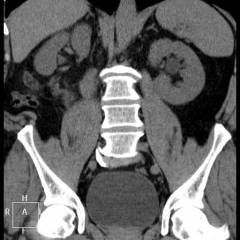

Компьютерная томография Чаще всего компьютерная томография при раке прямой кишки назначается в том случае, если после проведения УЗИ и рентгеновского исследования получают противоречивые данные.

Во время компьютерной томографии получают снимки, представляющие собой послойные срезы тазовой области. На них хорошо видна прямая кишка и соседние органы.